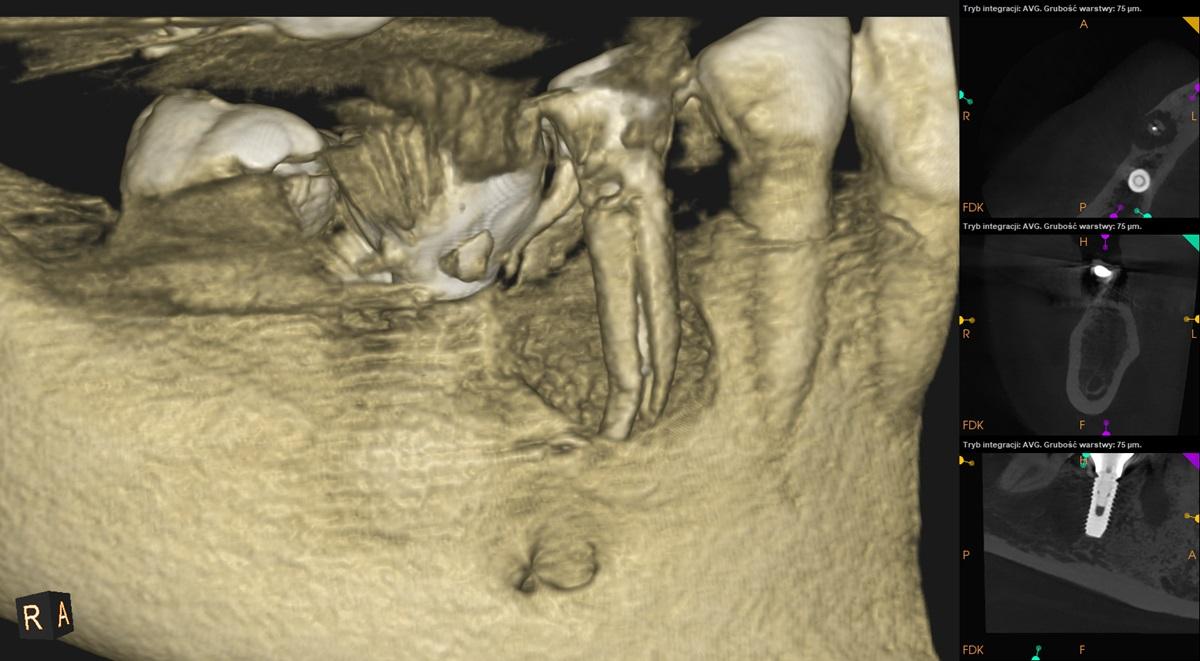

Tomografia szczęki i żuchwy, strona prawa.

Ząb 45 – po leczeniu kanałowym. Widoczne pionowe złamanie korzenia. Zanik tkanki kostnej wokoł korzenia obejmujący blaszkę zbitą po stronie przedsionkowej.